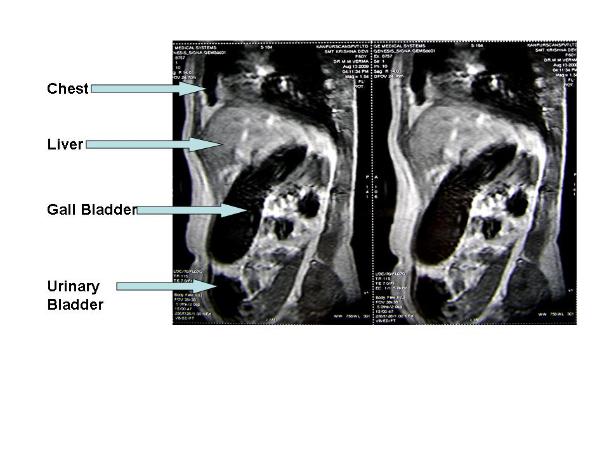

| Largest Gall Bladder removed through SINGLE HOLE Surgery |

| CT Scan |

| Gall Bladder after surgery Its size is equal to almost whole of abdomen |